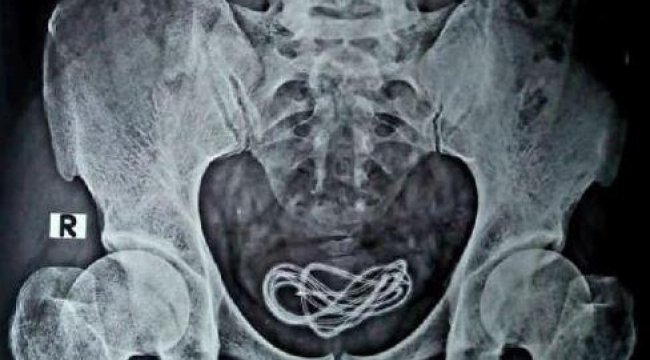

Hindistan'da bir kişinin mesanesinden bir metre uzunluğunda şarj kablosu çıktı

Hindistan’da karın ağrısı şikayetiyle hastaneye giden ismi açıklanmayan bir kişinin mesanesinde şarj kablosu tespit edildi. Özel operasyonla kişinin vücudundan çıkarılan şarj kablosu tıp dünyasını da şaşırttı.

Hindistan'ın Assam eyaletinde tıp dünyasını şaşkına çeviren bir olay yaşandı. Olay, Hindistan’ın Assam eyaletindeki Guwahati kentinde meydana geldi. 30 yaşında olduğu belirtilen bir kişi, karın ağrısı şikayetiyle hastaneye gitti. Çekilen röntgende, kişinin mesanesinde yaklaşık bir metre uzunluğunda bir şarj kablosunun olduğu görüldü. ÖNCE YUTTUM DEDİ, SONRA GERÇEK ORTAYA ÇIKTI Hindistan medyası, karın ağrısı şikayetiyle hastaneye giden kişinin doktorlara, “Şarj kablosunu yuttum” dediğini duyurdu. Doktorlar ameliyat sırasında şarj kablosunun, kişinin cinsel organından mesanesine girdiğini tespit etti. Ameliyatı gerçekleştiren Dr. Walliul Islam, “Yaklaşık 25 yıldır cerrahım ancak şu ana kadar bir ameliyatta ilk kez böyle bir durumla karşılaştım” dedi.